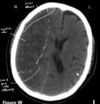

most common type of **lacunar** stroke: * often caused by occlusion of (...) artery * results in interruption of blood flow to **posterior** limb of (...) * presents with (...)

* often caused by occlusion of **lenticulostriate** artery * results in interruption of blood flow to **posterior** limb of **internal capsule** (which is where corticobulbar and corticospinal fibres pass through) * presents with **CONTRALATERAL hemiparesis** of **(lower) face, arm and leg**